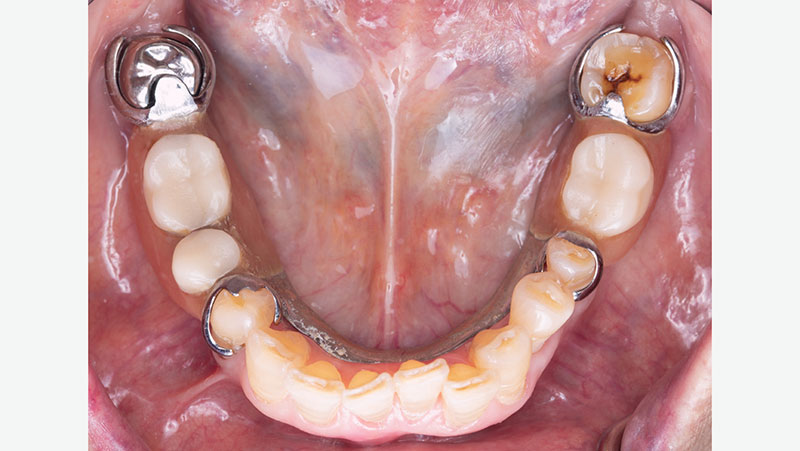

partial over final crown

Partial over final BruxZir crown.

Quality Control at Glidewell

As part of the lab’s quality control process, Glidewell supplies a 3D-printed model and a removable pattern of the partial along with the final crown. This is done in order to check the path of insertion, confirm proper seating and verify engagement with the crown. The photos below show an example of a 3D partial duplicate and model that were supplied with a final crown.